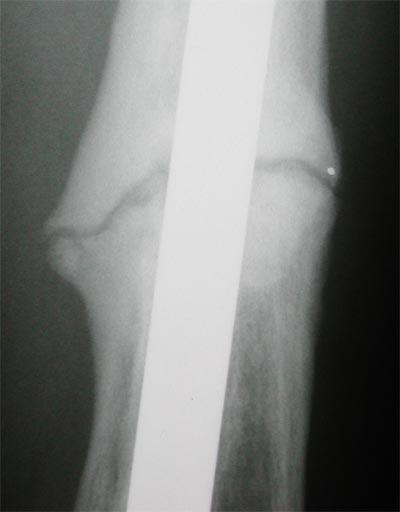

June 30, 2005 X-ray update

Again, things are feeling better, and this time the doctor even thinks he sees signs of progress, slow that it is. Left image is May 5, and on the right is June 30. The gaps are not changing much from the front view, but you can see where the space in between looks like is has more bone showing through. See the Lateral View to see what is happening there.